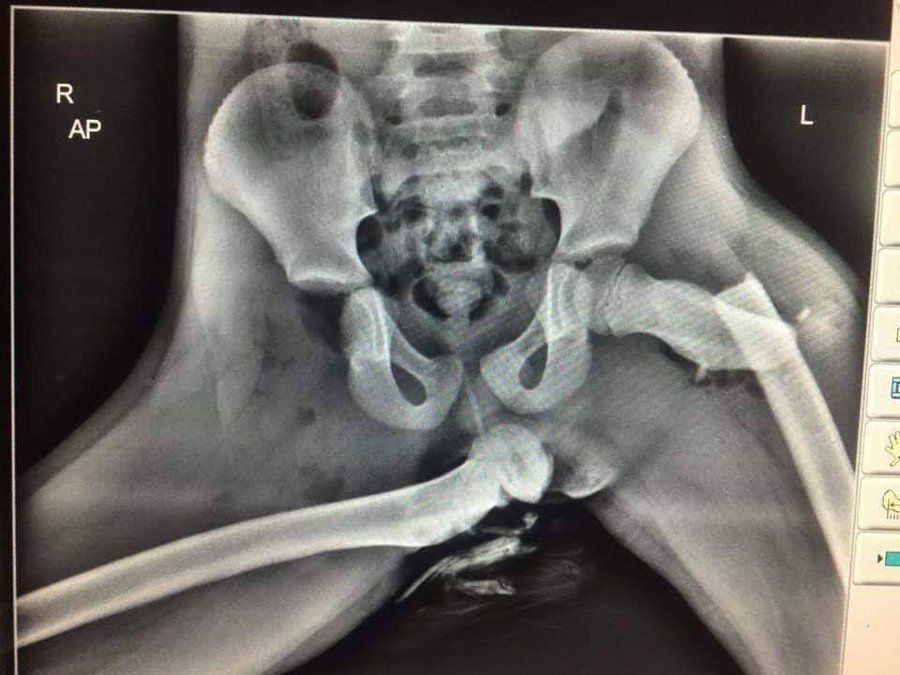

▲一名女子坐副駕時因把腳翹在前方置物箱上,導致發生車禍時,2腿嚴重骨折。(示意圖/翻攝自推特/@DPPGoSafeSgt121)

許多人坐在副駕駛座時,都喜歡把腳翹在前方置物箱上,但這樣的動作其實相當危險。時常分享醫療衛生相關案例的IG帳號「med.index」近日貼出一張駭人的X光照,有患者把腳放在前方置物箱上不幸發生車禍,導致兩條大腿骨都嚴重骨折,令人看得怵目驚心。

「med.index」12日在IG分享X光照,透露這名患者因為把腳翹在副駕前置物箱上又發生車禍,導致一邊大腿髖關節骨折,另一邊則是嚴重移位,「這就是為什麼我們永遠不應該把腳放在汽車儀表板上。」文章曝光後,馬上引起許多網友關注,紛紛留言,「真的無法想像這個的痛苦程度」、「真擔心這個人的生殖器」。

事實上,這張X光照的患者是一名英國女子,她先前坐在副駕駛座時,都會把雙腳放在前方置物箱上,即使丈夫曾出言勸阻,但她還是不在意,沒想到之後真的發生嚴重車禍,安全氣囊爆出猛烈力道,讓她的腿骨(股骨)完全從髖關節的髖臼上脫落,位移到了坐骨下方,戳出皮膚再插進屁股,留下了嚴重的後遺症。